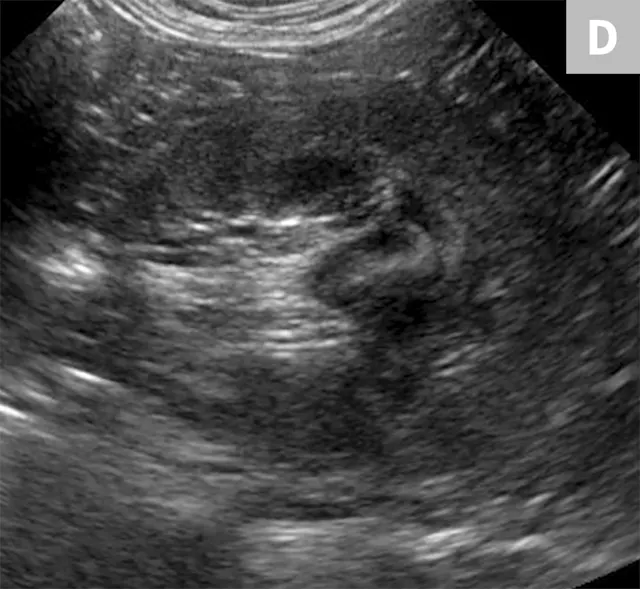

Ureteral calculi are a common cause of ureteral obstruction; localization of ureteral calculi is imperative prior to choosing appropriate management. While ureteral calculi have been reported as the most common cause of ureteral obstructions, other causes such as iatrogenic ligation, blood clots, tumor, strictures (congenital and acquired), solidified blood stones, and a circumcaval ureter have been reported.4-7

The obstruction can be located at any point of the ureter and can vary in severity. Normal ureters are typically not seen on ultrasonography due to their small size. The easiest way to locate a dilated ureter is to trace the ureter from the renal pelvis. In most cases, the ureter is dilated proximal to the site of an obstruction and tapers to a more normal appearance distal to the site of obstruction. Imaging can also reveal retroperitoneal effusion which can result from ureteritis and possible urine leakage.

Clinical signs associated with ureteral calculi may range from chronic non-specific signs to acute or chronic renal failure. The presence of hydronephrosis can be highly suggestive of a ureteral obstruction (Figure 6).